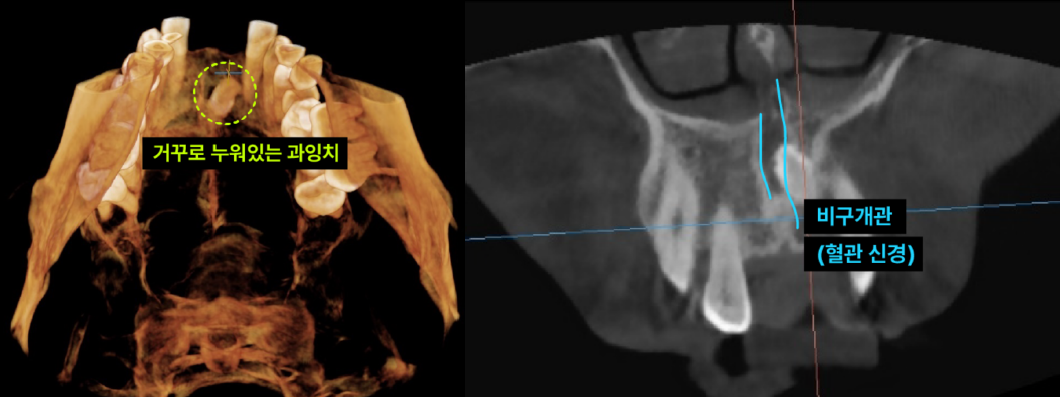

이백점치과의 정밀 진단 환자의 과잉치는 입천장 뼈 속에 거꾸로 누워있었고, 중요한 신경과 혈관이 지나는 '비구개관(Incisive Canal)'을 침범한 상태였습니다. 이처럼 민감한 부위의 매복 과잉치를 제거할 때는 비구개신경 손상이나 출혈에 각별히 주의해야 합니다. 이백점치과는 최신 장비를 활용한 정밀 진단으로 이런 디테일까지 놓치지 않습니다.